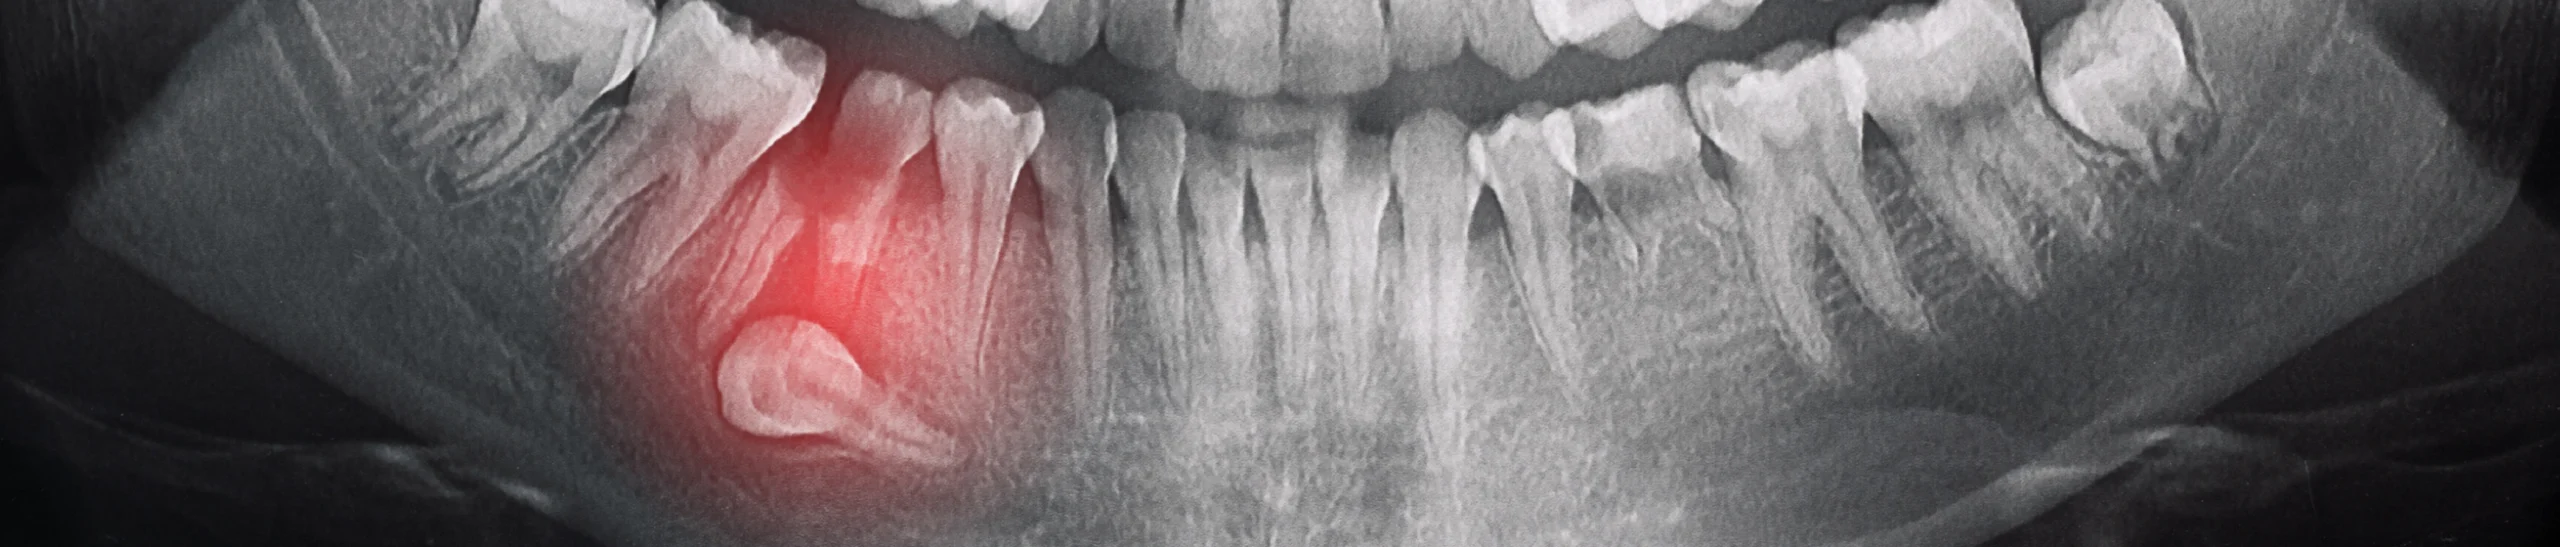

Les anomalies telles que les dents incluses, l’agénésie ou les dents surnuméraires ne provoquent pas toujours de gêne immédiate. Elles peuvent parfois être découvertes par hasard, lors d’un examen de routine ou d’une radiographie panoramique. Néanmoins, certains signes peuvent inciter à consulter :

Le dépistage précoce repose sur des examens cliniques réguliers, complétés par des radiographies panoramiques aux âges stratégiques, généralement entre 7 et 9 ans. Ce suivi permet :

- De repérer une dent incluse et d’évaluer son impact potentiel sur les dents voisines.